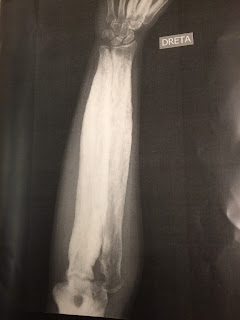

Radiografía anteroposterior del húmero derecho en la que apreciamos una hiperostosis en la diáfisis y metáfisis de este, respetando las epífisis. También podemos observar una disminución del canal medular de dicho hueso.